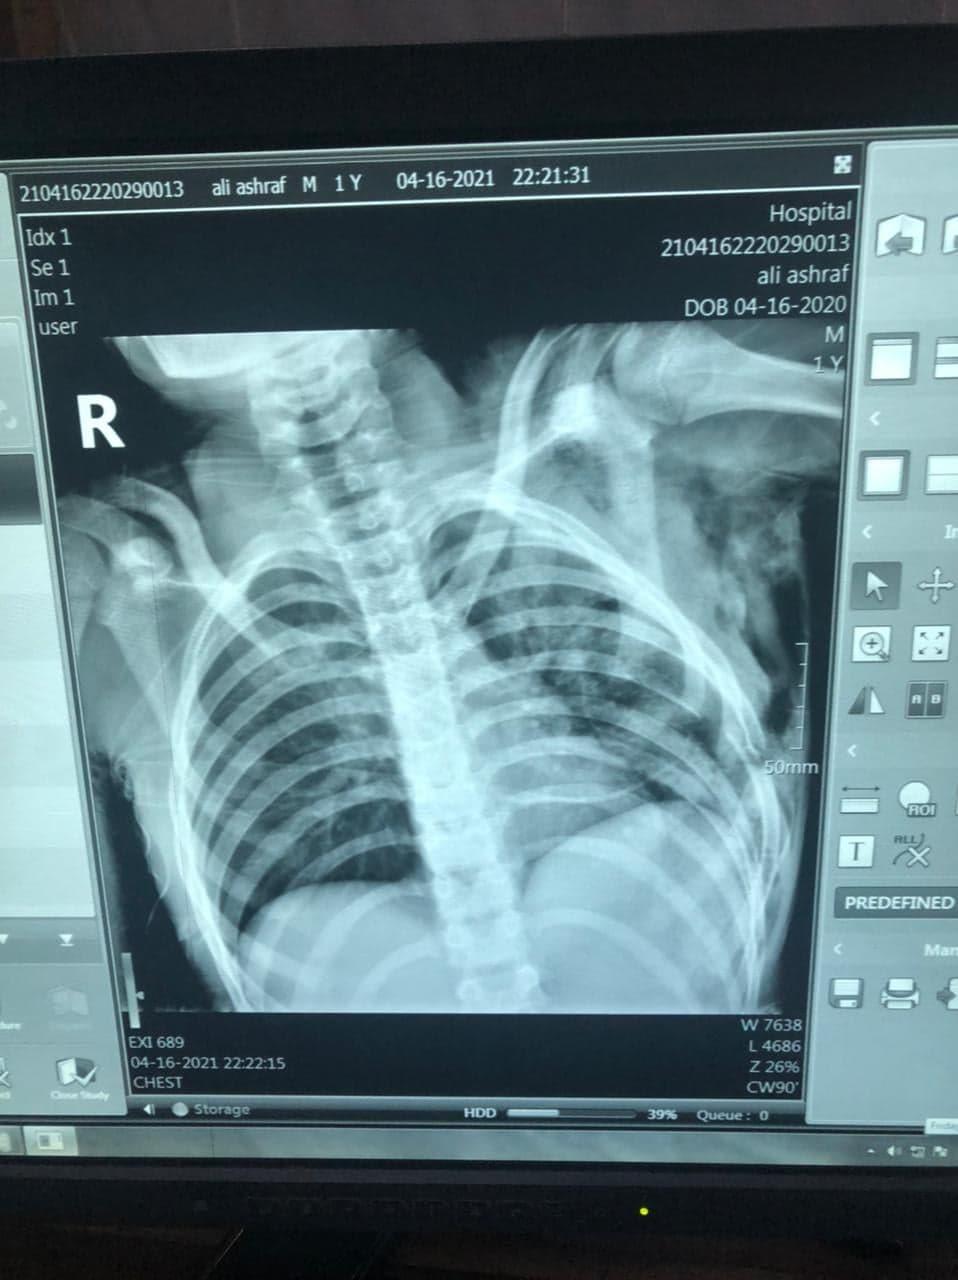

وتابع: بالكشف الطبي وعمل الفحوصات اللازمة تبين وجود جروح عميقة بالصدر، وتكسير بالضلوع، وخروج للرئة مع نزيف واسترواح هوائي، وجرى نقله إلى غرفة العمليات.

وأوضح جودة، أن فريقًا طبيًا مكونًا من الدكتور محمد رمضان، أخصائي الجراحة، يعاونه الدكتور رمضان ربيع، أخصائي الجراحة، والدكتور هيثم الشريف، طبيب مقيم الجراحة، نجح في إنقاذ حياة المريض وإجراء عملية لإغلاق الجرح وإصلاح التهتك مع تركيب أنبوب صدري، ونقله إلى الرعاية المركزة لحين استقرار الحالة ومتابعة واستكمال العلاج.